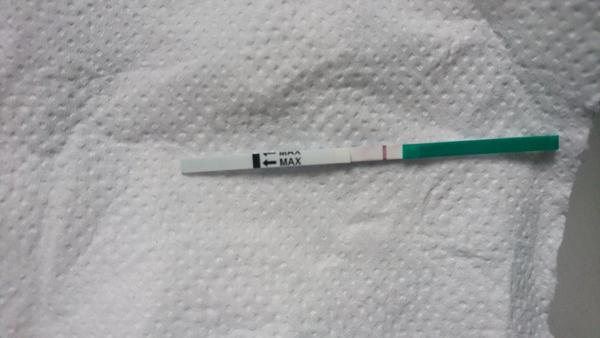

Ahojte, test je belsi, nez sneh co nam od rana pada 😕 muz mi odchadza na tri mesiace do cudziny, bol to nas posledny pokus pred cestou. Vsetkym vam prajem, nech sa vam splni vas senn, my sme sa dohodli, ze to zatial nechame tak. Drzte sa a dakujem 🏵🏵🏵